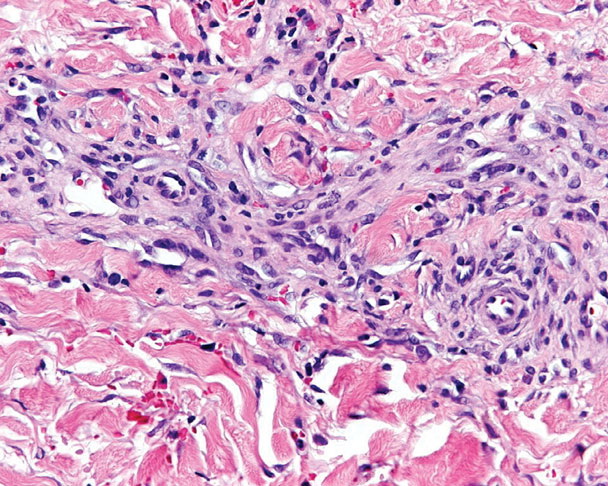

HISTOPATHOLOGY

The histopathology of KS is dependent on the stage of KS development. Early patch-like lesions exhibit rather discrete histopathologic changes, consisting mainly of an increase in the number of dermal vessels, outlined by slightly irregular endothelial cells (Fig. 128-5). These vessels, located mainly in the superficial dermis are parallel to the skin surface, are frequently slightly irregular, and may form bizarre slits and clefts. In the surrounding skin focal hemosiderin, deposits and extravasated erythrocytes can be found as well as a moderate inflammatory infiltrate. Important differential diagnoses of this stage include lymphangioma and granulation tissue.

The pathology of KS plaques is more characteristic and reveals extensive vascular proliferation at all levels of the dermis with multiple dilated and angulated vascular spaces dissecting the collagen leaving a spongy network of collagen tissue. A characteristic sign of KS papules is the presence of solid cords and fascicles of spindle cells arranged between the jagged vascular channels. This biphasic angiomatous and solid tumor morphology changes to a clear-cut sarcomatous morphology with progression of the disease.

Nodular lesions consist predominantly of spindle cells arranged in bundles and interlacing fascicles and interspersed, irregular, slit-like vascular spaces without endothelial linings. Advanced lesions may display pronounced pleomorphism, nuclear atypia, and mitotic figures. At the periphery of solid tumors, (lymph) angiomatous-like portions of KS with bizarre vascular lumina and intravascular and extravasated erythrocytes, as well as siderophages, may be preserved. Erythrocytes, which appear as eosinophilic globules, are trapped within the slits and clefts formed by the spindle cells and erythrophagocytosis are occasionally observed. As in all other stages of KS, a moderate inflammatory infiltrate consisting of lymphocytes, histiocytes, plasma cells, and, sporadically, neutrophils is regularly present.